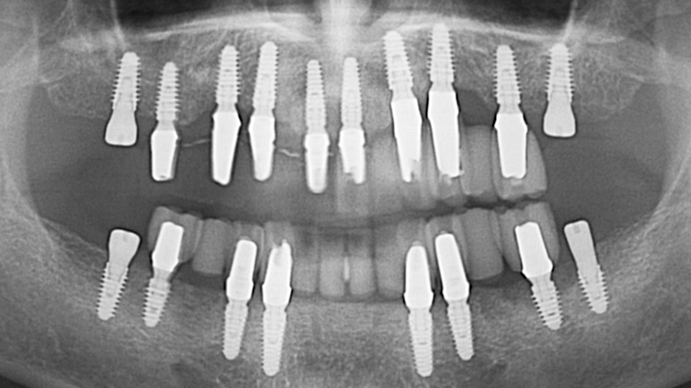

Clinical case: Preview the final goal first, make the ideal treatment plan, then realize it using the appropriate tools

- Courtesy of Dr. Sang Tack Lee, Korea -

Dr. Sang Tack Lee, edentulous, digital full mouth prosthetics, digital guided surgery, #11, #13, #14, #16, #17, #21, #23, #24, #26, #27, #33, #34, #36, #37, #43, #44, #46, #47, guided surgery, flapless, AnyRidge, R2GATE, Mega ISQ, MEG Torq, MEG Engine, R2GATE Full surgical kit

AnyRidge implant system, R2GATE Guide, R2GATE full surgical kit , Mega ISQ